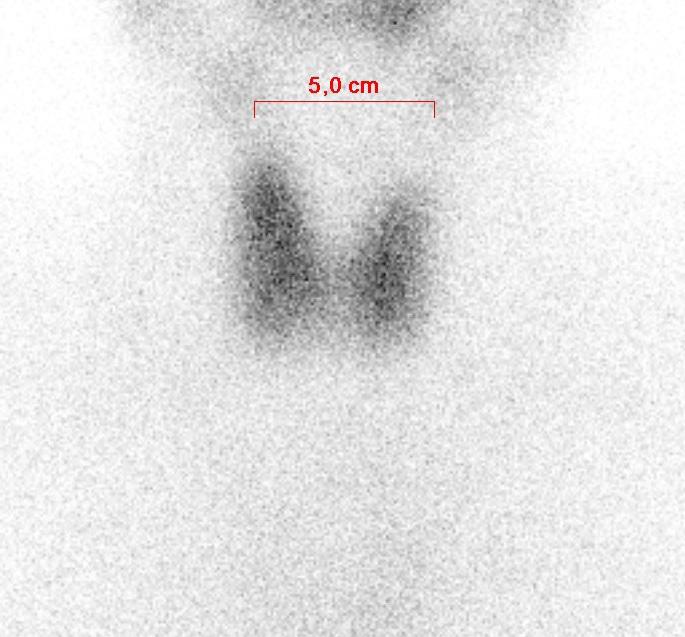

Scintigraphie thyroïdienne

La scintigraphie thyroïdienne est un examen qui permet l’étude de la structure et du fonctionnement de la glande thyroïde.

La caméra sera positionnée près de votre corps, sans jamais vous toucher. Elle prendra une image de votre thyroïde pendant environ 10 minutes.